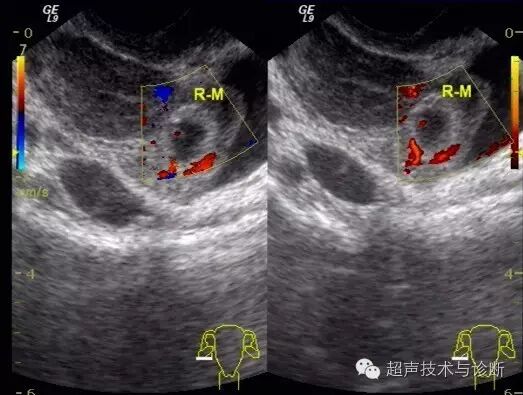

4、超声检查如下(2016。02。01):子宫形态大小正常,宫腔内见一不规则囊性结构,大小4x2cm,透声差,未见双环征及胚芽结构,CDfi未见血流。双侧卵巢可见,右侧附件区可见一囊性结构,大小3x2cm,其内可见胚芽及心管博动。

入院血HCG及超声检查图像如下;